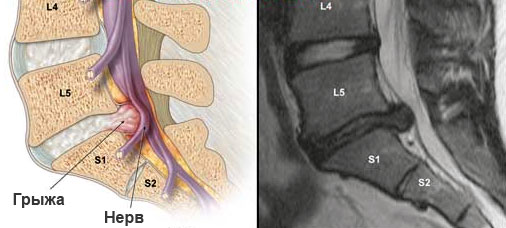

Размер грыжи, который играет решающую роль в принятии решения о необходимости операции, зависит от отдела позвоночника, в котором она расположена. Протрузии в поясничном и грудном отделах до 12 мм могут успешно лечиться консервативно, что дает пациенту шанс избежать операции. В то же время для шейной грыжи размер в 7 мм уже считается критическим, и вероятность хирургического вмешательства в таких случаях значительно возрастает.

Показания к операции не ограничиваются только размером грыжи; они также зависят от ущемления спинного мозга или нервных корешков. Хирургическое вмешательство может быть рекомендовано, если длительное консервативное лечение не приносит облегчения, и болевой синдром сохраняется.

Размеры протрузий поясничного отдела

Наиболее распространенной является грыжа в поясничной области позвоночника. Она проявляется следующими симптомами:

Когда протрузия достигает 12 мм и более, обычно требуется операция. Это особенно актуально, если происходит сжатие нервных корешков, известных как конский хвост. При их сдавливании у пациента может возникнуть паралич нижней части тела. В таких ситуациях операция по удалению грыжи позвоночника становится единственным способом сохранить или восстановить двигательную активность пациента.